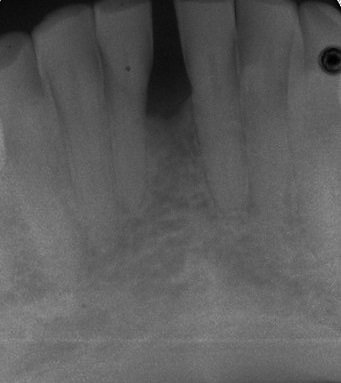

Siete años después del tratamiento regenerativo, tal y como se aprecia en la radiografía 2, el incisivo ha recuperado el hueso perdido (raíz rodeada de nuevo hueso) y sigue en la boca y con un pronóstico muy favorable. El paciente está muy satisfecho de seguir disfrutando de su diente.

- Radiografía 2